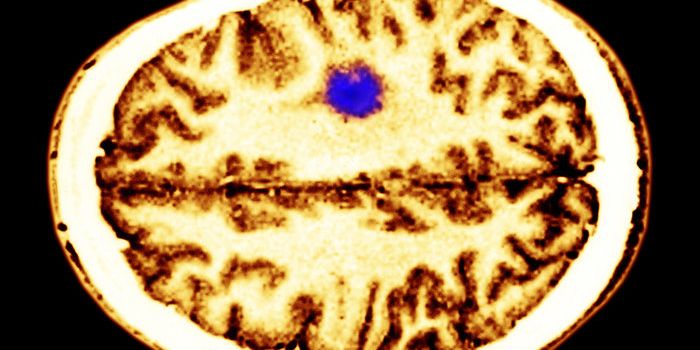

JUL 22, 2015NeuroscienceTreating an aggressive brain tumor may have come one step closer to reality recently as a company developing a novel the ...

APR 24, 2015CancerThe simple act of thinking can accelerate the growth of many brain tumors.That's the conclusion of a paper in Cell publi ...